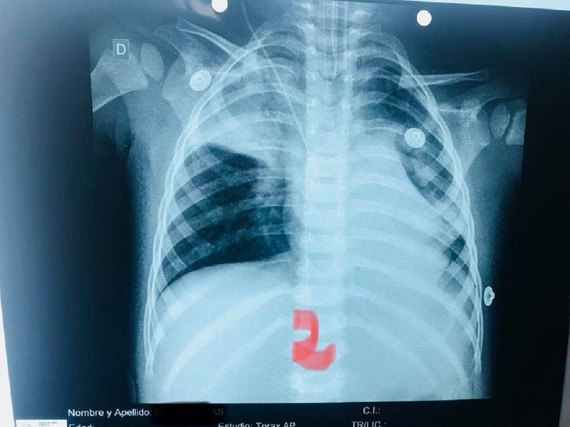

Señaló además que durante el procedimiento, la semilla se movió al otro pulmón, lo que pudo haber sido fatal, ya que le causó un cuadro de neumonía.

Indicó que durante todo el procedimiento el paciente estuvo con asistencia respiratoria artificial, porque ya no respiraba por sí mismo.